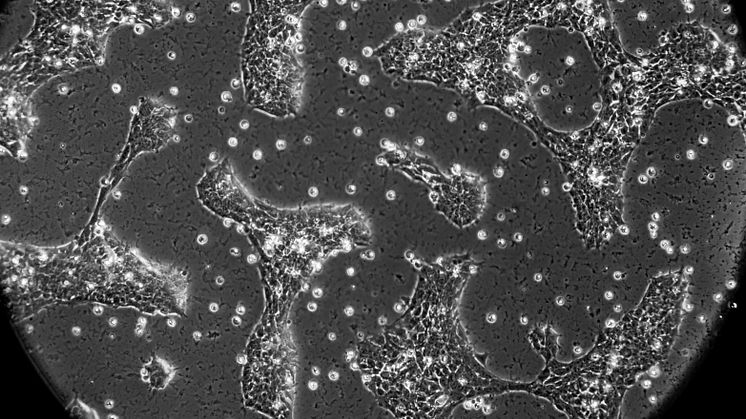

Celler odlade i laboratoriet uppträder mycket annorlunda än celler i kroppen. Redan efter några dagar är förändringen så stor att den kan påverka tolkningen av en studie, visar forskning vid universiteten i Linköping och Edinburgh.

– Vi tog hudceller från musembryon, odlade dem i petriskålar och kontrollerade deras genuttryck över tid. Vi blev mycket överraskade av hur snabbt och omfattande cellerna påverkades. Förändringen startade nästan omedelbart, säger Colm Nestor, forskare vid Centrum för individualiserad medicinering, LiU och försteförfattare till artikeln.

När DNA i de ursprungliga muscellerna jämfördes med dem som odlades i laboratoriemiljön, fann forskarna att cellernas så kallade epigenom – kemiska modifieringar som avgör vilka gener som är ”på” eller ”av” – mycket snart blev omprogrammerat. Mer än 7 000 gener påverkades.